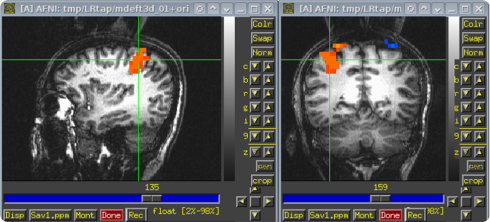

The second case demonstrates that errors may also harm people indirectly. For example, errors in the MRI software call into question about 40,000 scientific studies. Over decades, neuroscientists and cognitive psychologists have used the AFNI, SPM, and FSl statistical programs to analyze the fMRI data. As it turned out, due to incorrect algorithms, these programs may return 70% of false positive results, instead of the expected 5%.